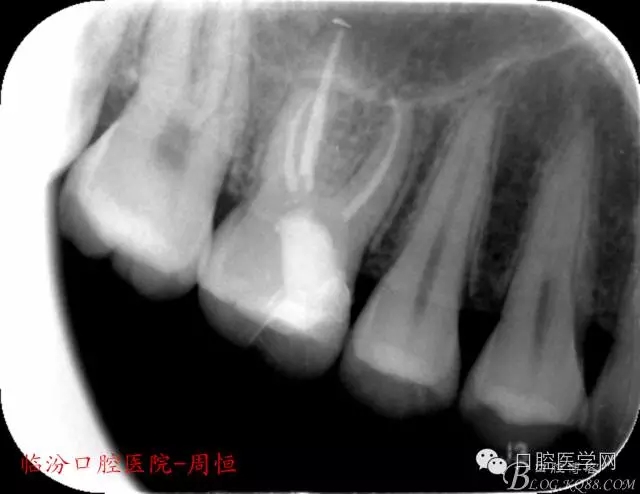

X 示:近中低密度陰影達(dá)髓腔,牙根未見異常。

圖1 X示 術(shù)前

圖2 X示 根充后